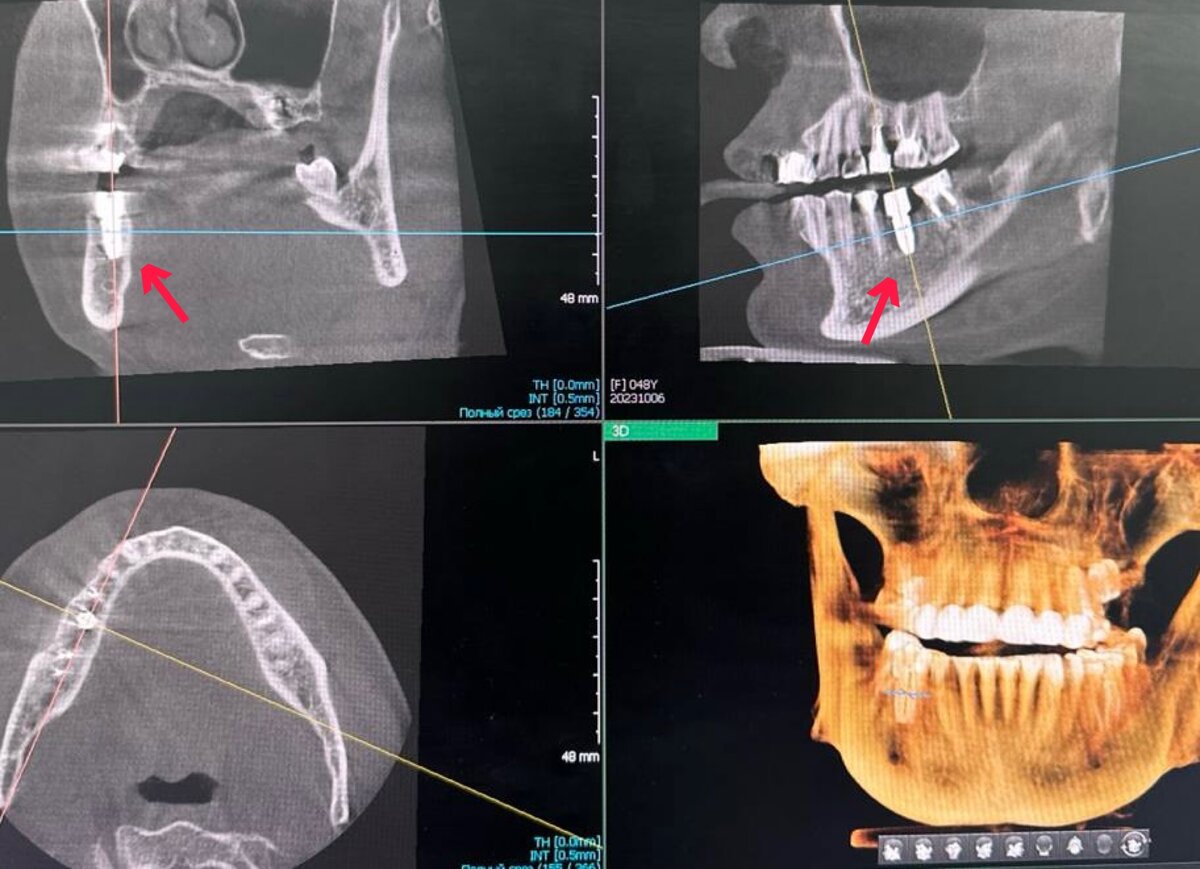

• Зуб можно сохранить, если он имеет здоровые корень (не пораженный кариесом) и ткани вокруг него, а также при отсутствии трещин и наличии феррул-эффекта. В этом случае проводится лечение каналов и восстановление зуба с помощью коронки или вкладки.

Для того, чтобы сохранить зуб и сделать терапию эффективной, современная стоматологическая клиника должна быть оснащена всем необходимым оборудованием и материалами как для эндодонтического лечения (сохранения собственного зуба), так и для качественной имплантации. В клинике Regale решение о дальнейшем лечении или установки импланта принимается врачом-стоматологом после тщательного обследования пациента и оценки всех факторов. В своей работе наши специалисты применяют гнатологический подход.

Гнатологический подход учитывает состояние не просто зубов, но и челюстно-лицевой области в целом. Он основан на знаниях анатомии, физиологии и биомеханики челюстно-лицевой зоны и позволяет проводить более точную диагностику и лечение заболеваний зубов и челюстей.